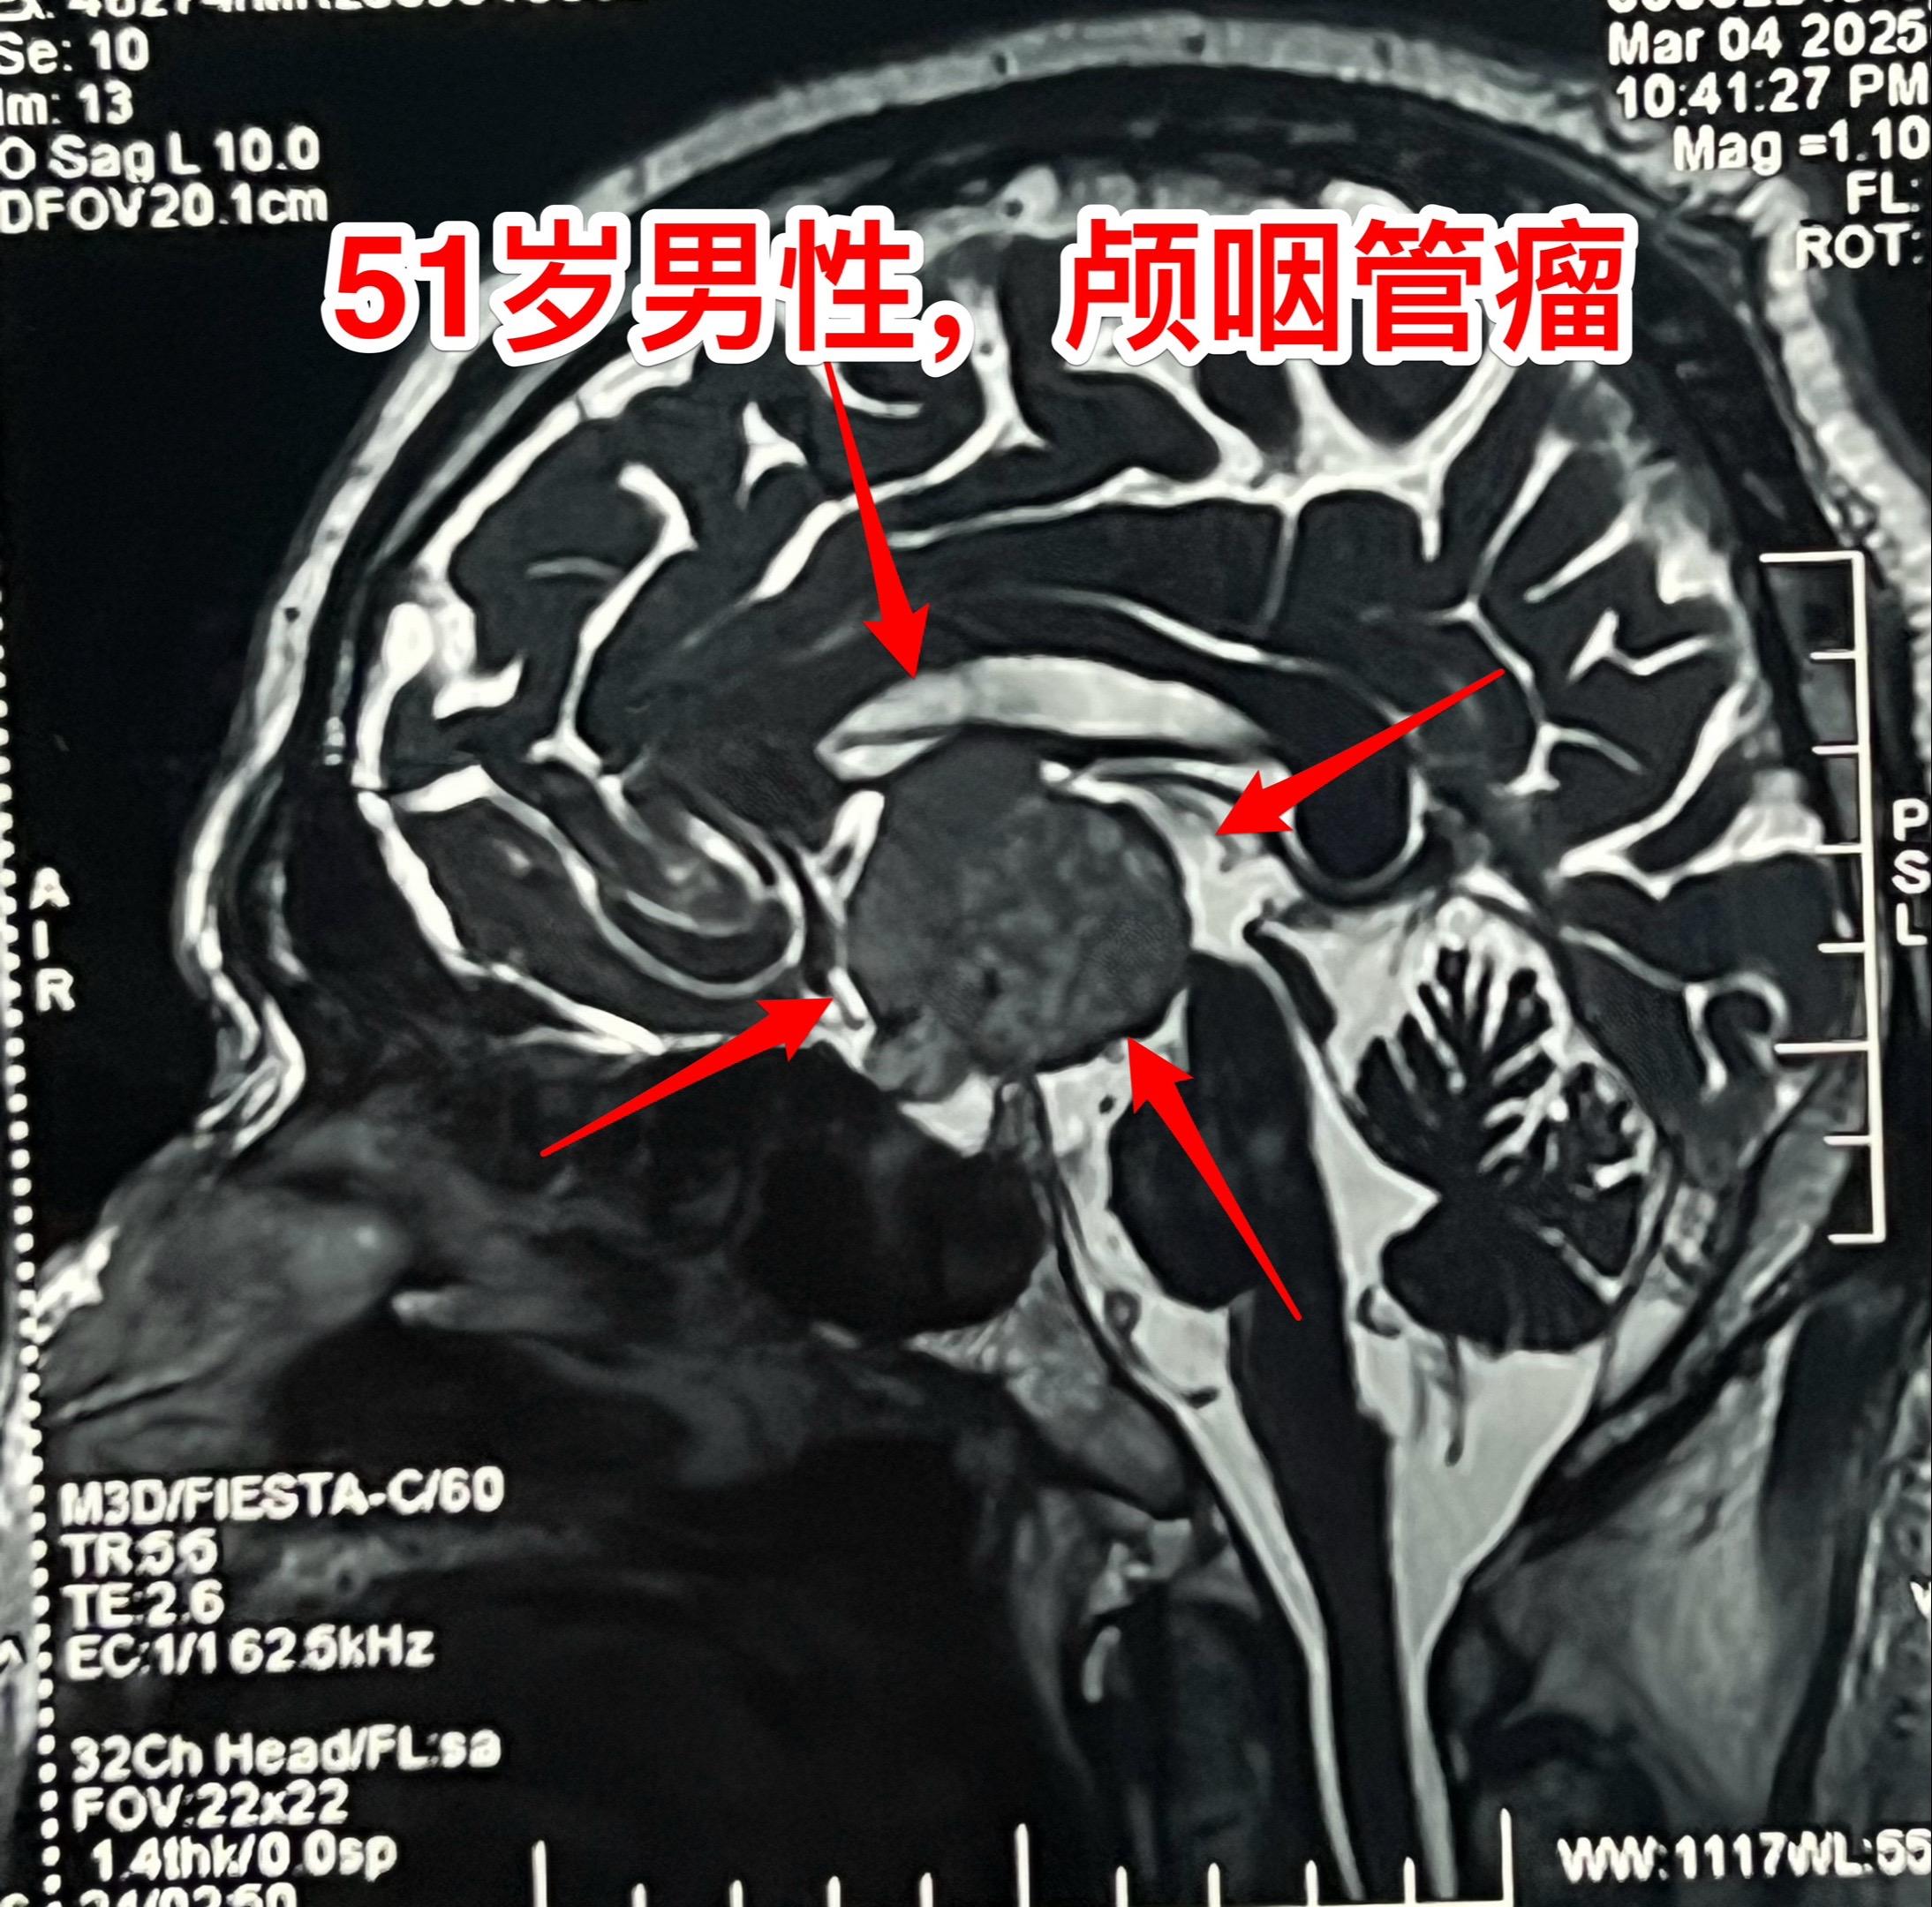

昨日一个颅咽管瘤手术+一个胶质瘤手术。昨日第一个手术:51岁男性,卡车司机,因记忆力下降、视物模糊检查发现颅咽管瘤,见图。肿瘤主体位于第三脑室内,实性肿瘤,有小块钙化斑。术中见肿瘤呈肉乎乎的,有细小钙化斑。肿瘤完全切除,垂体柄保留约40%。术后CT未见术区出血。 第2个病人是大同市女性,39岁,因头痛、呕吐到医院检查发现左侧脑部肿瘤,考虑为高级别胶质瘤。这个胶质瘤内血管粗大、扩张 怀疑有动脉瘤,是个血供十分丰富的肿瘤。术中看见肿瘤内血管粗大,像动脉瘤一样扩张,肿瘤呈暗红色,质地较韧,血供丰富